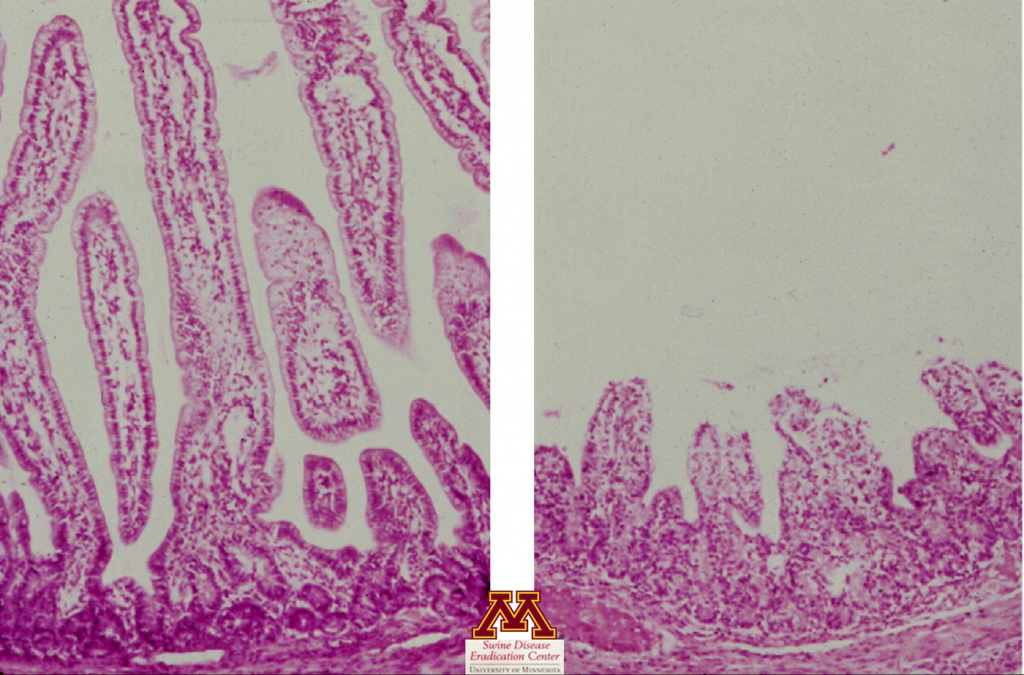

Istopatologia

- Valuta la presenza di lesioni tissutali (atrofia dei villi dell'intestino tenue) che possono fortemente suggerire la presenza di malattia.

- Conferma l'atrofia dei villi che suggerisce un'enterite virale